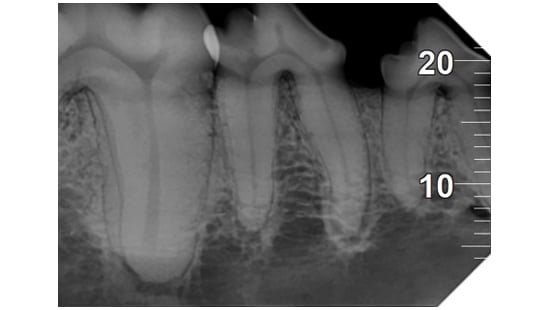

Analyse auf hohem Niveau

Das mit der zugehörigen Software integrierte System bietet hochmoderne Analysewerkzeuge und eine Auswahl spezifischer Filter, um die Lesbarkeit der Bilder gemäß den klinischen Anforderungen zu verbessern: